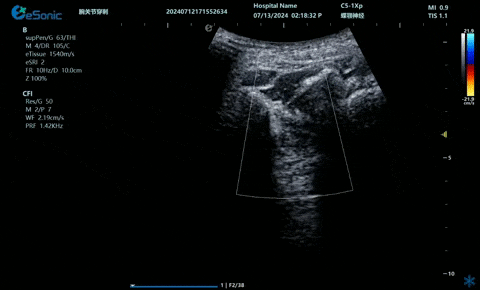

超声引导下肋间神经阻滞切面